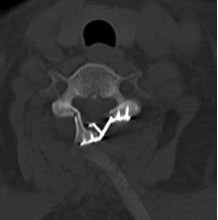

术后

术后次日患者四肢肌力逐渐恢复至4+级,目前患者除双下肢仍感觉有少许麻木感外,四肢肌力已恢复正常。出院时患者及家属对我院骨科团队及省人医帮扶专家表示充分的肯定和由衷的感谢。